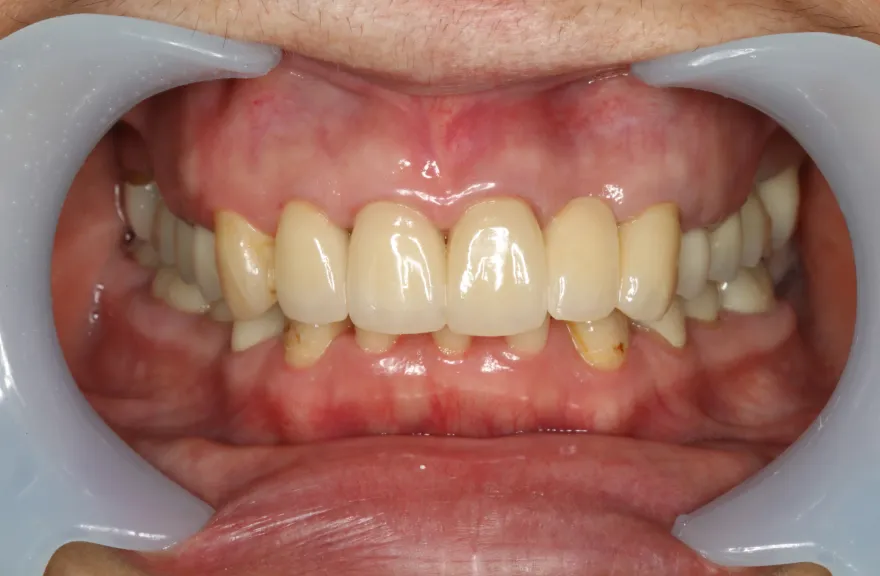

【治療例 5】上の歯がグラグラで困っている 62歳

- 相談内容

- 数年前に全体的に治療したが、上のつながっている歯がグラグラして噛めないということで来院されました。

- 治療費用・方針

-

上顎は5本の歯を保険のブリッジ治療で連結してある状態でした。どの歯の状態も良くなく、今回なんとか治療を行ったとしても近いうちに再びトラブルを起こしてくることが予想されました。

下顎は9本の歯が残っており、虫歯はあるものの差し歯として使える状況でした。

しかし、患者さんとの話し合いの中で、「数年前に行った治療なのに再び全てやりかえないといけないのは単純にしんどい。もうやりかえのないようにしたい」という患者さんの強い思いが伝わってきました。

今回で完全に治療をやり切ってしまい、今後は最小限の介入で歯科と付き合えるよう、上下顎残っている歯の全ての抜歯、必要な本数のインプラント埋入、上顎は総義歯形態で対応することとしました。 - 治療のリスク